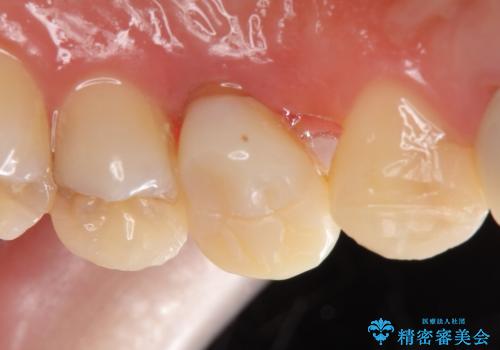

オールセラミッククラウン 歯牙の挺出後の補綴

- 左上3、4番の見た目が気になるためセラミックにしたいといらっしゃった方の症例です。

左上4の補綴物を除去したところ縁下歯質だったため、歯牙の挺出を提案し行いました。

挺出終了後は歯肉切除および骨外科により歯周組織を整え、オールセラミッククラウンによる補綴を行いました。